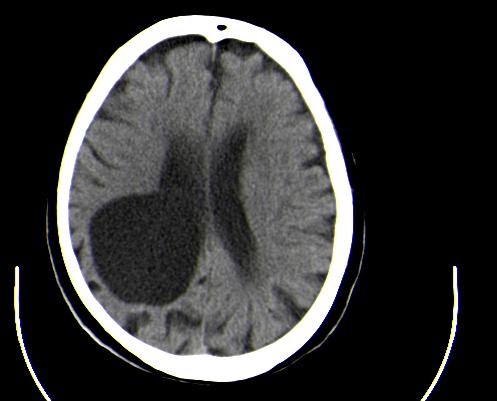

患者男性,67岁,头晕摔倒后来医院就诊,患者诉平时体健,否认有颅内病变史

定位:右侧脑室三角区扩大,呈球形,侧脑室颞角扩大,右侧脑室内占位:

定性:蛛网膜囊肿可能性大;

定位:右侧脑室三角区扩大,呈球形,侧脑室颞角扩大。

考虑:1、右侧侧脑室三角区室管膜囊肿?皮样囊肿?

2、脑萎缩。

神经上皮囊肿为先天性疾病,可发生在脉络丛、脑室内、脉络膜裂,少数位于脑质内,侧脑室三角区最为常见。按发生部位和囊壁的细胞学类型可有不同的命名。位于脉络丛者为脉络丛囊肿,常两侧同时发生。脑室内者为室管膜囊肿,多位于侧脑室三角区。脉络膜裂囊肿可以是神经上皮囊肿,也可以是蛛网膜囊肿。 囊肿呈脑脊液样低密度,边界清楚整齐。患者多无症状,有症状者多为头痛、癫痫发作。囊壁很薄,ct一般不能显示,囊壁无钙化。囊肿可有占位效应,表现为相应部位的脑室或脉络膜裂较对侧扩大,脑实质受压,一般不引起脑水肿。增强:囊肿及囊壁均无强化。

与蛛网膜囊肿的鉴别:蛛网膜囊肿好发于中颅窝、鞍上、半球、后颅窝、侧裂,脑室内少见,临床表现和影像学与神经上皮囊肿无明显差别。主要靠发病部位鉴别。